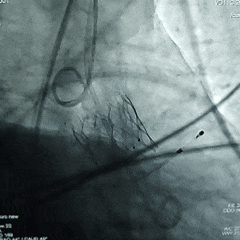

术中情况回顾

主动脉根部造影

18mm球囊预扩张

瓣膜初始定位

瓣膜展开至工作位

瓣膜工作位评估

瓣膜工作位多角度评估

瓣膜稳定脱钩

瓣膜脱钩后造影,瓣膜形态不佳决定后扩张

20mm球囊后扩张

瓣膜后扩后造影测压,无压差